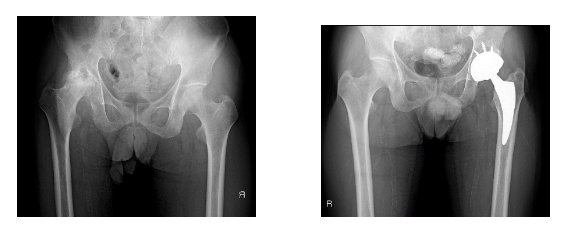

【 股関節疾患および骨盤外傷】

股関節の疾患では,主に臼蓋形成不全症、変形性股関節症、大腿骨頭壊死症を扱っています。 臼蓋形成不全症、変形性股関節症や大腿骨頭壊死症には人工股関節置換術を施行しています。術後脱臼の合併症を減らすべく、従来の後方アプローチだけではなく、前方アプローチも積極的に取り入れています。

また、変形性股関節症に対しては多血小板血漿(PRP)による治療にも積極的に行っています。